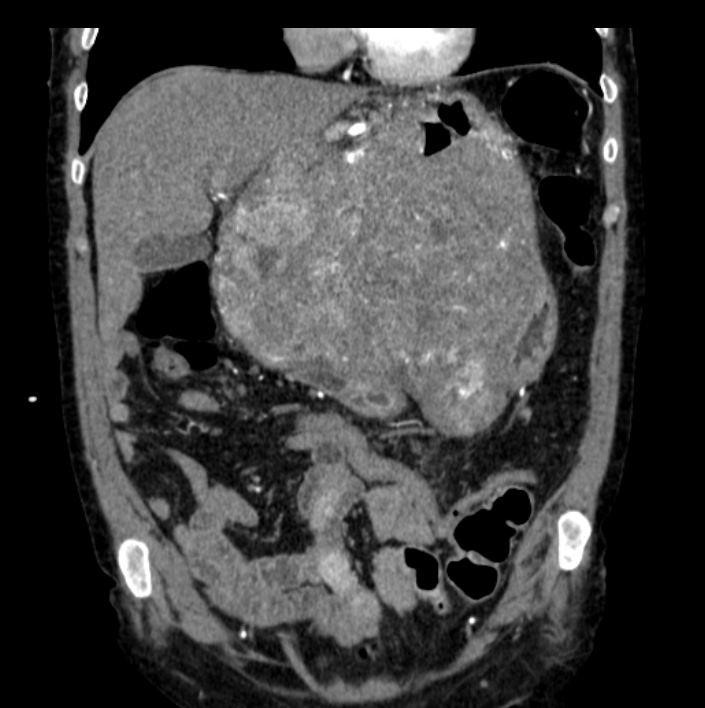

КТ-исследование абсцесса малого таза: Визуализация и диагностика

Раздел: Фотоальбом решений